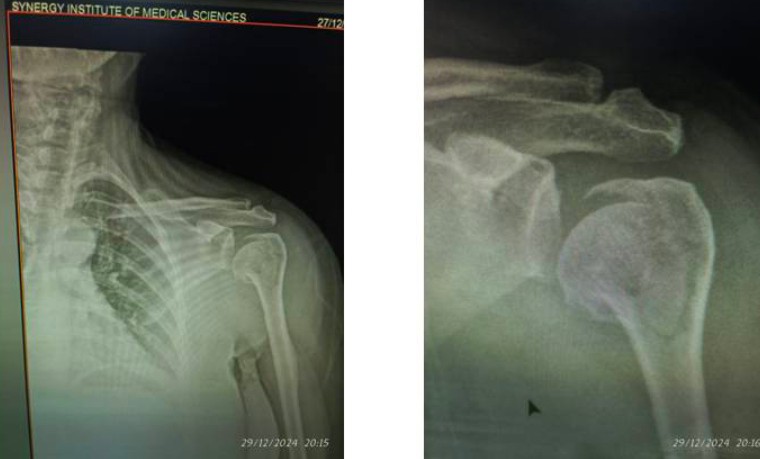

*अभी वॉट्सअप पर एक ताजा प्रकरण जिसमे सिनर्जी अस्पताल में महिला मरीज 27 दिसम्बर को सिनर्जी हॉस्पिटल में चोट लगने के बाद इमरजेंसी में आयी जिसको अस्थि रोग विशेषज्ञ डॉ प्रवीण मित्तल के द्वारा देखा गया फिर उसका एक्स- रे कराया गया और बताया गया की हड्डी कई टुकडो में टूटी है और ऑपरेशन की सलाह दी गयी लेकिन इसके अगले दिन व्हाट्सएप पर भ्रामक एवं झूठा मेसेज डाला गया, कि हड्डी टूटी हुई नहीं थी, और मरीज को ऑपरेशन की गलत सलाह दी गयी है और यह भी कहा गया की मरीज को जब मैक्स हॉस्पिटल दिखाया गया तो पता चला की हड्डी टूटी नहीं थी एवम आरोप लगाया की डॉक्टर प्रवीण स्वार्थवश गलत डायग्नोसिस कर के ऑपरेशन की गलत सलाह दे रहे है*

*वास्तविकता यह थी कि उक्त महिला रोगी को जब मेक्स अस्पताल में डॉ हिमांशु कोचर को दिखाया गया, तो उन्होंने भी सी टी स्कैन करा कर हड्डी को चार हिस्सों में टूटा बताया एवं ऑपरेशन की सलाह दी।*

*उस मरीज का 3 जनवरी को ग्राफिक एरा हॉस्पिटल में डॉ राहुल अग्रवाल द्वारा ऑपरेशन हुआ और प्लेट भी डाली गई जैसे की डॉ प्रवीण मित्तल व मेक्स अस्पताल के चिकित्सक ने कहा था।*

*इसी के साथ सारे एक्स – रे और रिपोर्ट्स नीचे संलग्न हैं।*